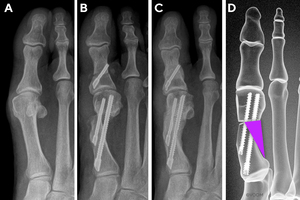

First Metatarsal Regeneration Type III: Robust callus formation with first metatarsal regeneration (Figure 4).

The area where bone healing occurs with new MIBS is located in a triangular zone lateral to the first metatarsal shaft and proximal to the subcapital osteotomy, which we herein define (and coin) as the regeneration triangle (Figure 1). Distinct patterns of metatarsal healing and regeneration may occur in this regeneration triangle. We classified them into our newly developed FMR classification system with three types (FMR Types I, II, III) (Table 1 & Figures 2-4), based on bone healing in relation to the MI anchor bone screw. The “anchor” screw is the dominant screw in the fixation construct of a new MIBS that connects the proximal metatarsal segment to the translated metatarsal head.22 Radiographic bone healing assessments were reviewed and graded, based on the anteroposterior radiograph; however, additional views were assessed to verify union when necessary.

New First Metatarsal Regeneration Classification System (Figures 2-4)